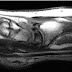

Se planifica el estudio con helice de 0.625 mm. abarcando todo el territorio toracico desde región supraclavicular, en dirección craneo caudal y hasta incluir ambas cúpulas diafragmáticas, teniendo especial cuidado con el FOV para incluir ambos músculos dorsal ancho.

Bomba de inyección automatica, con un caudal de 70 ml a 4 ml/seg. y usando técnica de smart prep, con roi en subclavia.

Saludos desde Panama. Fantasticas imagenes. Me gustaria saber como fueron adquiridas (protocolo)

Las he hecho con smart prep poniendo el roi en la arteria subclavia.

administrando contraste un volumen de 80cc a 3.5ml/seg.

helice de 0.625 mm